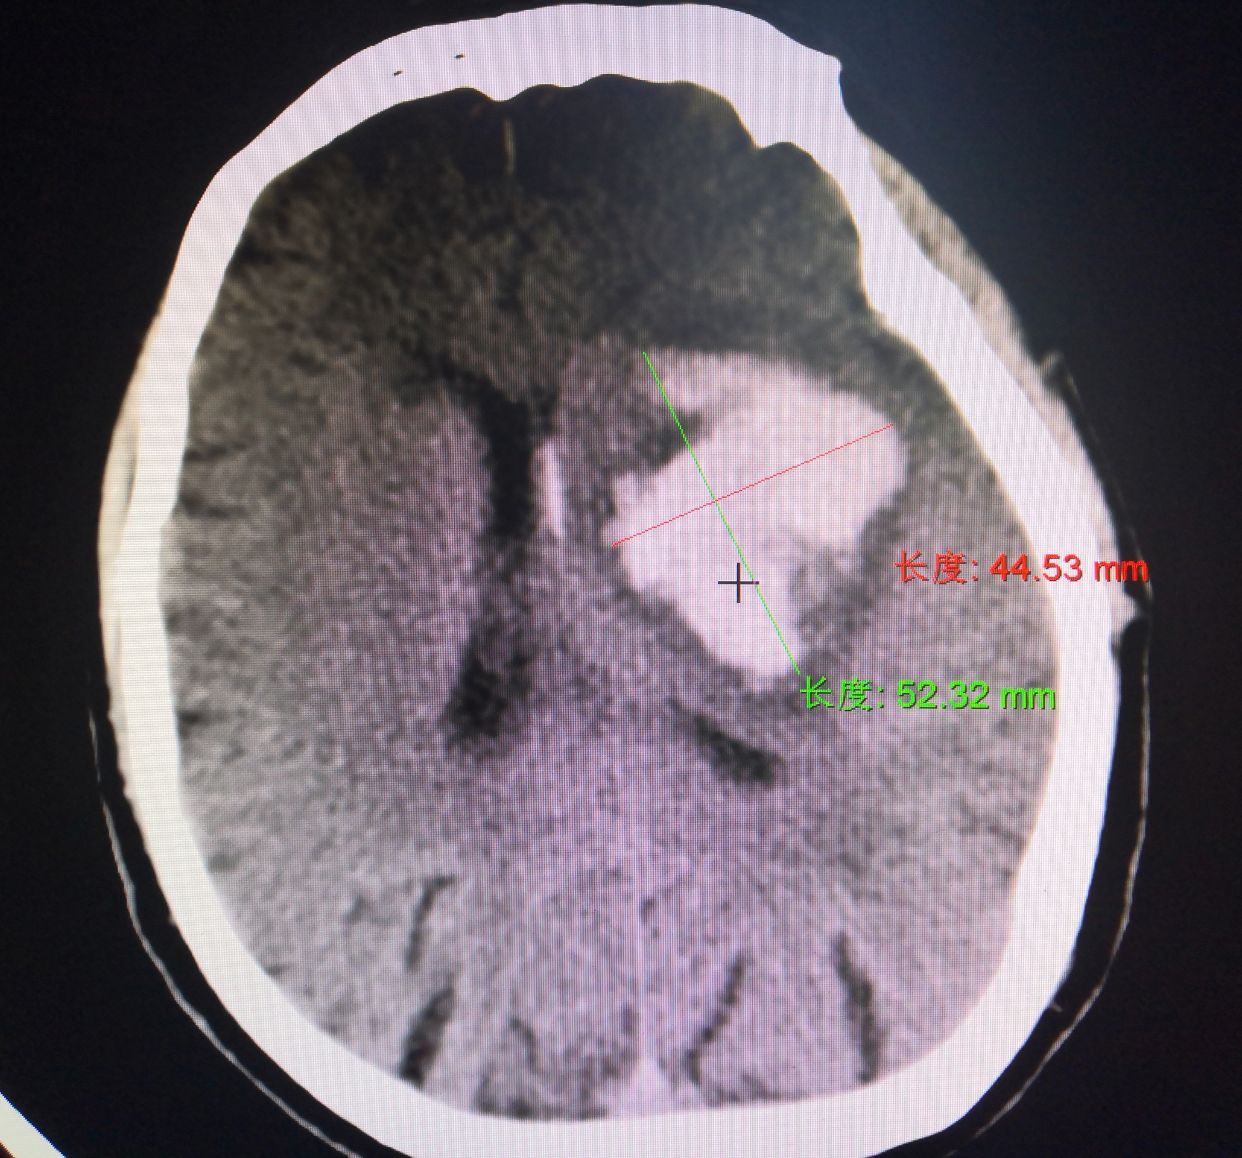

术前多田公式测量出血量约为63ml

确定穿刺置管方向